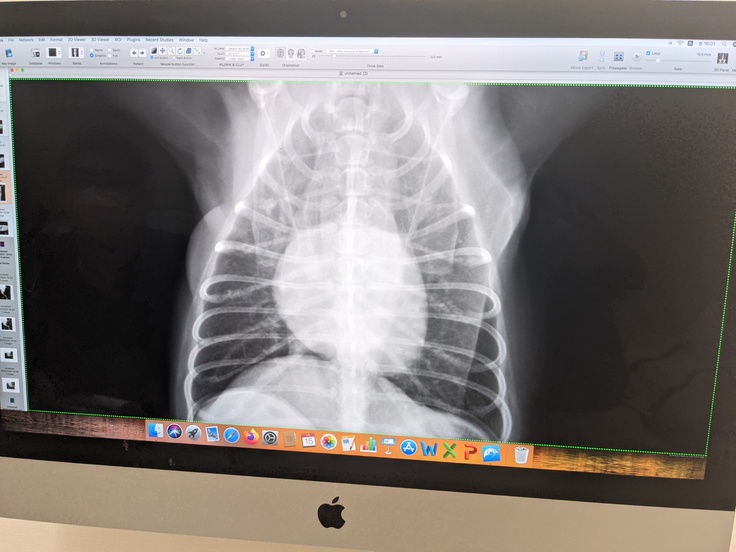

⚫レントゲン撮影は、7月15日に診察受けた時のものです。幸いに、肺に転移はみられないようでした。ご報告致します。

乳腺腫瘍の場合は、CTは撮らないそうです。

乳腺切除手術の術前検査は

・採血すみ

・レントゲン撮影すみ

・心電図すみ